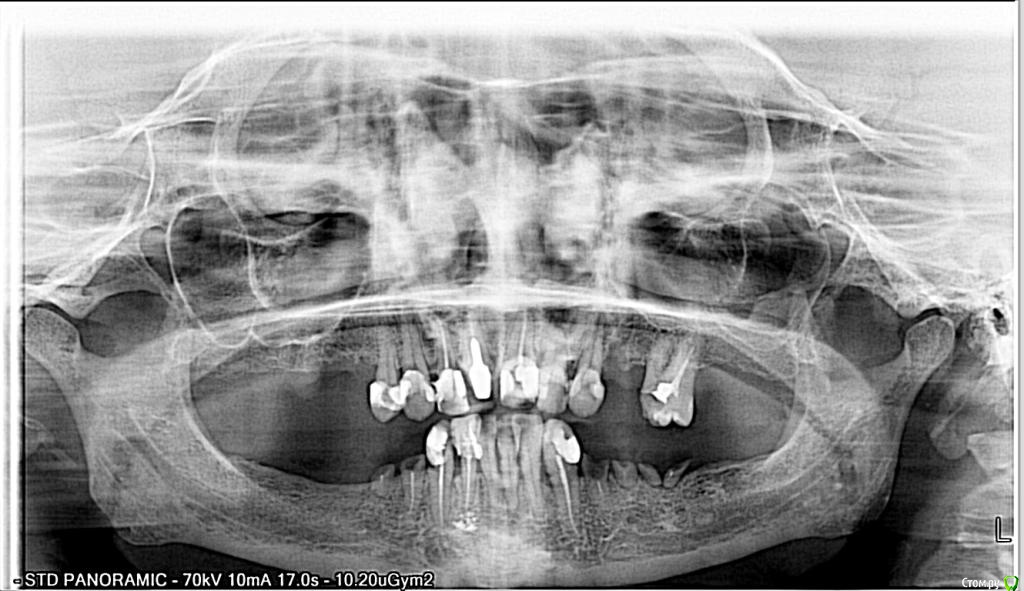

IngaK Опубликовано 26 декабря, 2014 Поделиться Опубликовано 26 декабря, 2014 Доброе время суток, уважаемые.Посмотрите пожалуйста снимок. Видите ли вы что-то криминальное, в т.ч. кисты и/или какие-либо источники воспаления, т.е. то, что нуждается в срочном вмешательстве.Сам снимок 17.12., на данный момент, 26.12. все корешки удалены.Большое спасибо за ответ. Ссылка на комментарий

faity Опубликовано 30 декабря, 2014 Поделиться Опубликовано 30 декабря, 2014 непонятный участок слева снизу, необходимо КТ.по остаткам зубов... либо оставлять сверху 6 передних и по 3 импланта с каждой стороны, либо сносить все зубы и делать все на 12 имплантах и балке Ссылка на комментарий

IvanK Опубликовано 30 декабря, 2014 Поделиться Опубликовано 30 декабря, 2014 если хочется что-то найти, нужно кт Ссылка на комментарий

faity Опубликовано 31 декабря, 2014 Поделиться Опубликовано 31 декабря, 2014 вы же в мос.обл. обитаете? найдите ближайщий офис пикассо, сделайте КТ на аппарате Vatech размер 12Х8,5 и выкладывайте ссылку сюдане реклама, своих пациентов часто туда отсылаю 1 Ссылка на комментарий